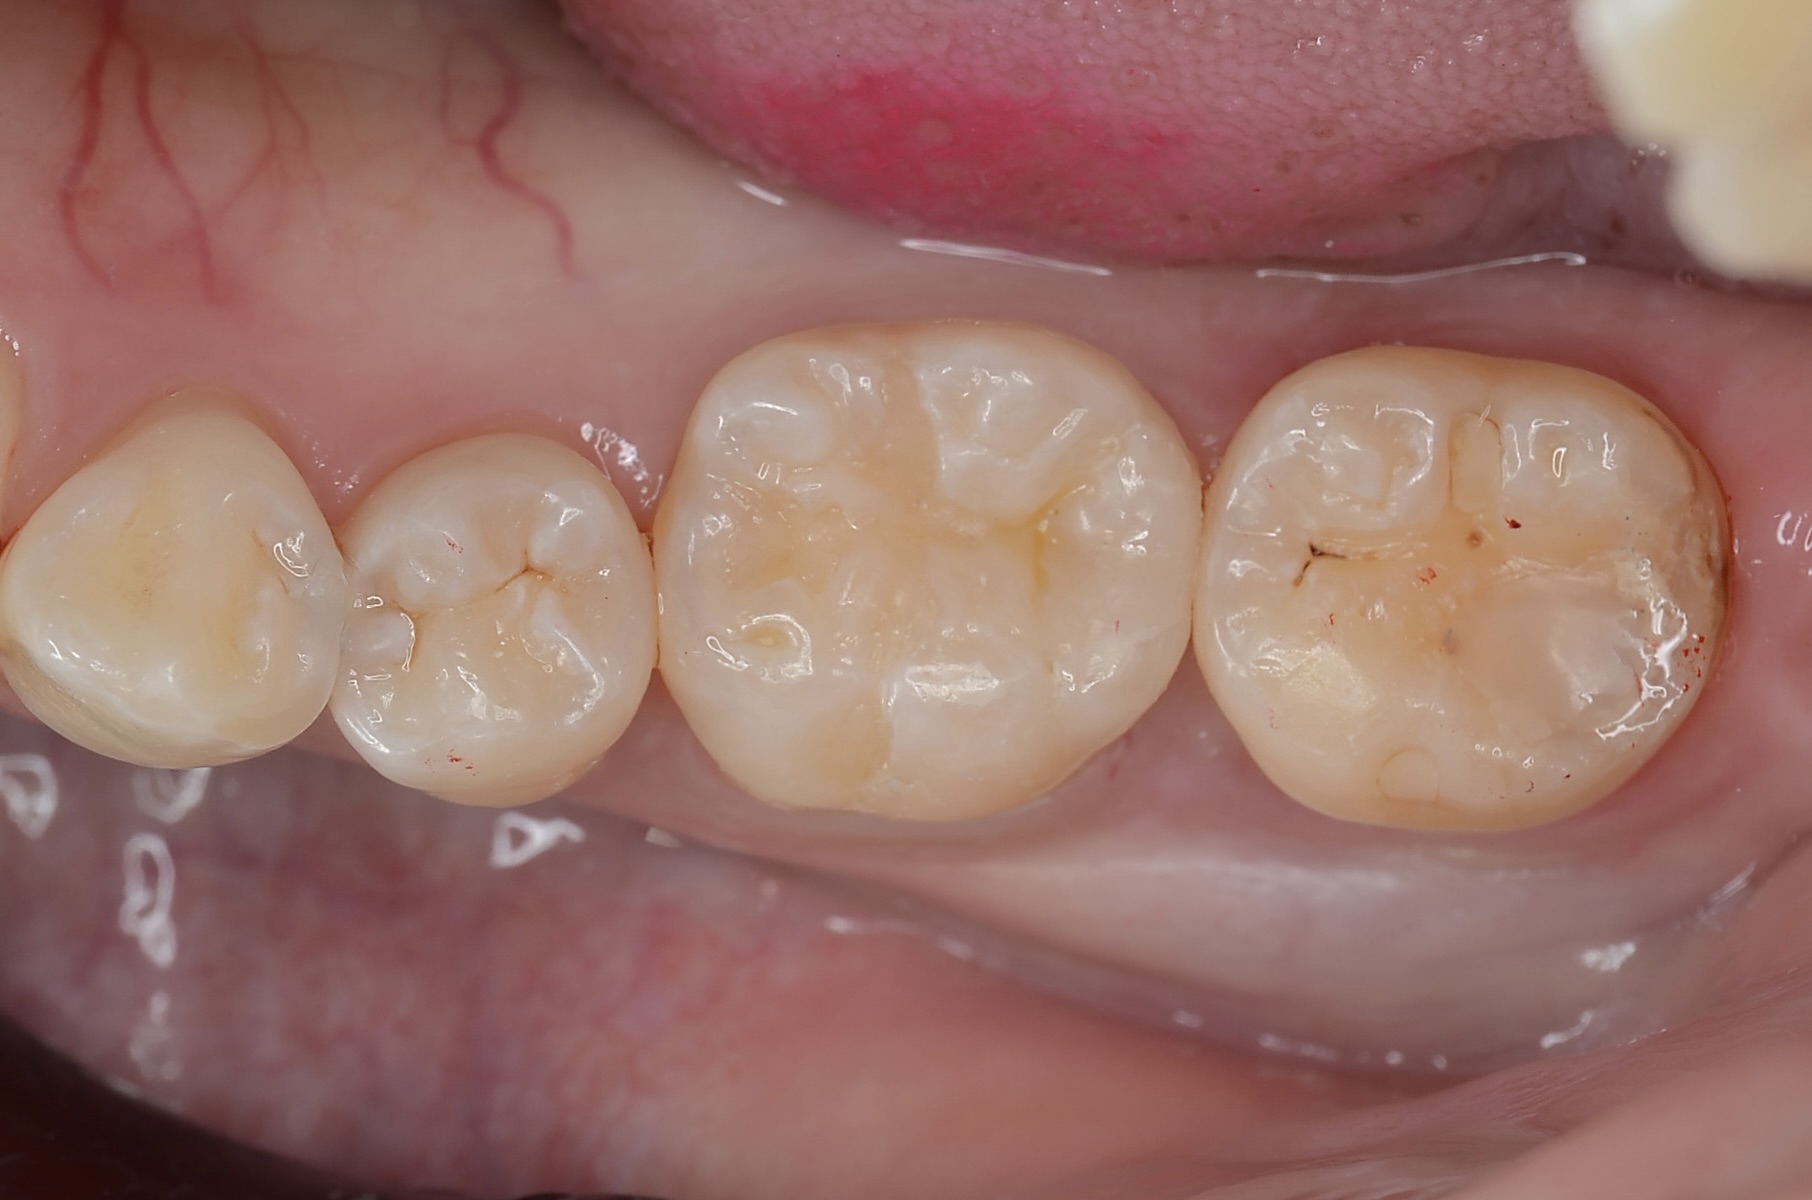

Before

6番の遠心隣接面が黒くなっています。 虫歯があります。痛みはなかったようです。 -

エナメル質がうっすら灰色になっている部分から、少し歯を削ってみると中が虫歯になっていました。 -